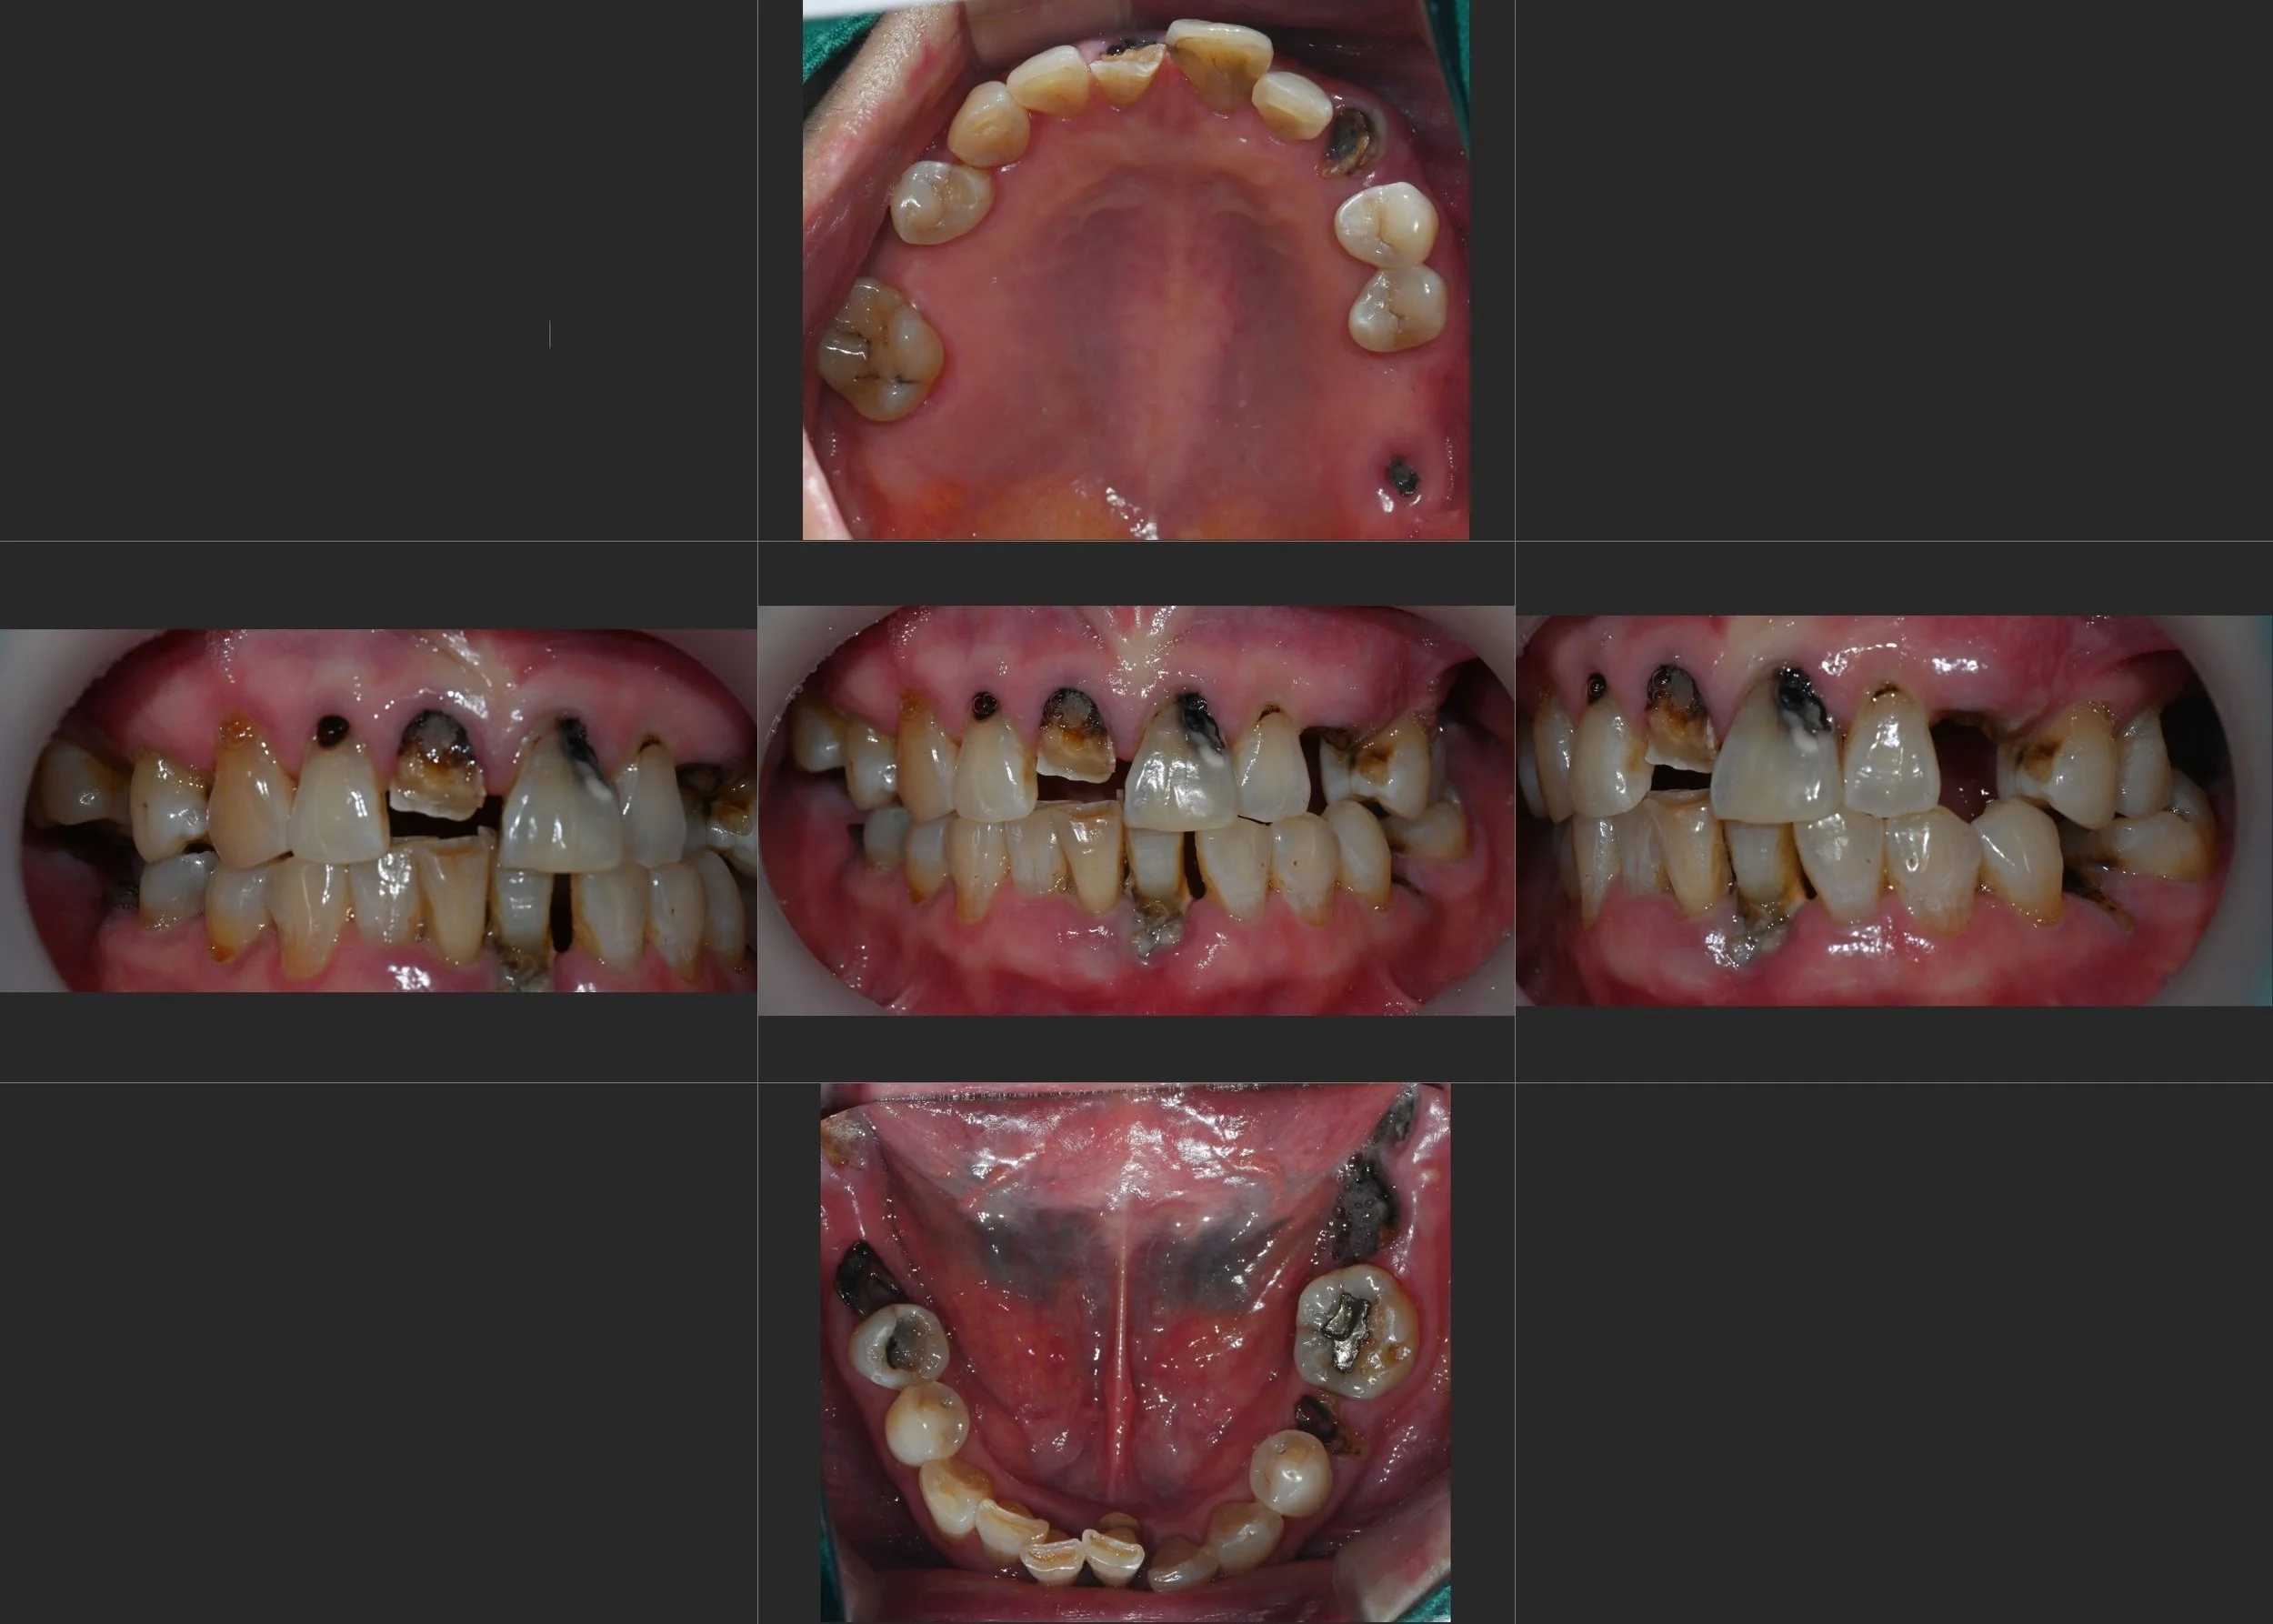

Reversing the effects of generalized rampant caries and occlusal collapse in a female patient in her 20s. A tooth-preserving, implant-assisted approach focused on stable VDO elevation and overcoming social anxiety.